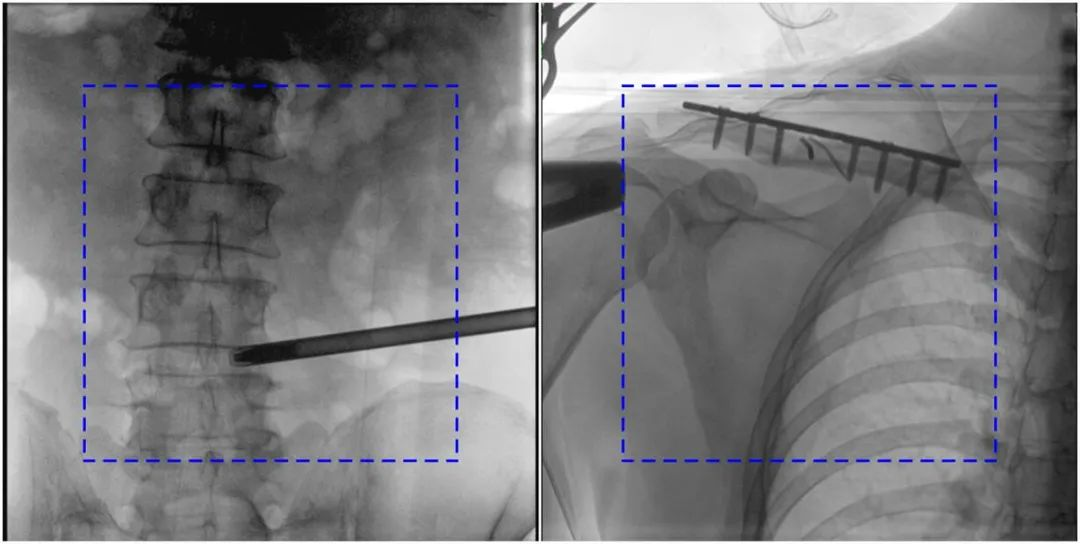

與傳統(tǒng)的21CM×21CM成像尺寸相比,普愛醫(yī)療大平板一體式C形臂具有30CM×30CM更大成像尺寸,能夠一次成像5.5節(jié)椎體,呈現(xiàn)更全面的影像信息,即便是手術(shù)經(jīng)驗(yàn)不豐富的年輕醫(yī)生也能通過圖像迅速判斷椎體節(jié)段、定位手術(shù)部位,避免因?yàn)橐曇安蛔愣斐傻亩啻味ㄎ?、反?fù)曝光,提高效率的同時(shí)避免過量攝入輻射。

普愛醫(yī)療大平板一體式C形臂圖像與傳統(tǒng)圖像對比(藍(lán)色虛線內(nèi)為傳統(tǒng)21CM×21CM平板的成像區(qū)域)